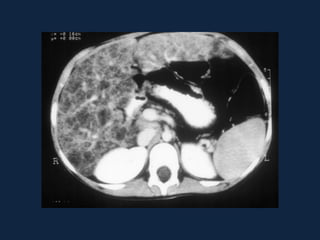

Hemangioma

► s/c: Lesões bem definidas, lobuladas, hipodensas ao parênquima e

isodensas aos vasos intra-hepáticos.

► c/c: (aspecto típico em lesões 2-10cm):

 Fase arterial: Realce periférico nodular e descontínuo, com áreas

nodulares ou globuliforme, da periferia para o centro da lesão. Centrípeto.

 Fase portal: Realce progressivo e centrípeto (da periferia para o centro).

 Fase tardia: Ocorre o preenchimento completo e homogêneo da lesão, com

realce persistente.

► Tempo de enchimento completo depende do tamanho da lesão

► Lesões pequenas (<2cm): enchimento completo rápido

► Lesões grandes (>10cm): preenchimento incompleto da lesão (presença

de trombos, áreas de fibrose e/ou necrose).